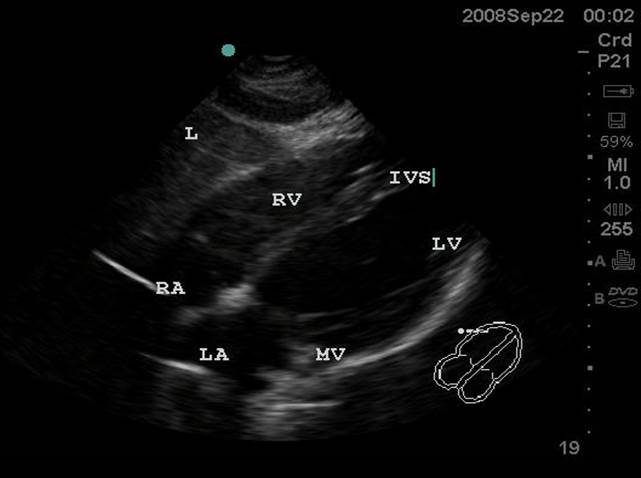

- Subxiphoid or Subcostal View: The liver is used as an acoustic window and is seen at the left of the screen and near field. The right ventricle being the most anterior is adjacent to the liver. The apex will be to the right of the screen. By fanning inferiorly, the inferior vena cava (IVC) is seen in short axis. Often the hepatic veins can be seen in the liver draining into the IVC.

- Figure 1. Subxiphoid View. RA = Right atrium. RV = Right ventricle. IVS = interventricular septum. LV = left ventricle. MV = Mitral valve. LA = left atrium. L = Liver

- Subxiphoid or Subcostal View: The liver is used as an acoustic window and is seen at the left of the screen and near field. The right ventricle being the most anterior is adjacent to the liver. The apex will be to the right of the screen. By fanning inferiorly, the inferior vena cava (IVC) is seen in short axis. Often the hepatic veins can be seen in the liver draining into the IVC.